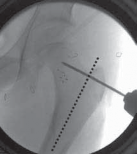

16. On the AP image the guide pin needs to be sufficiently proximal (superior) to provide enough room to permit the introduction of the seating chisel inferior to the guide pin (

TECH FIG 2A

).

17. On the frog-leg lateral view, the guide pin should lie in the middle of the femoral neck in line with the neck axis (

TECH FIG 2B

--- TECH FIG 2 • Intraoperative C-arm–guided insertion of the seating chisel for the blade plate.A. Insertion of the guide pin in the superior part of the neck at right angles to the long axis of the femur. B. Position of the guide pin along the midfemoral neck axis in the frog-leg lateral view. C. Position of the seating chisel parallel to the guide pin and perpendicular to the long axis of the femur. D. Position of the seating chisel parallel to the guide pin and along the midfemoral neck axis on the frog-leg lateral view. E. The seating chisel is backed out from its final position to disimpact the chisel before the osteotomy.Pr FiAE